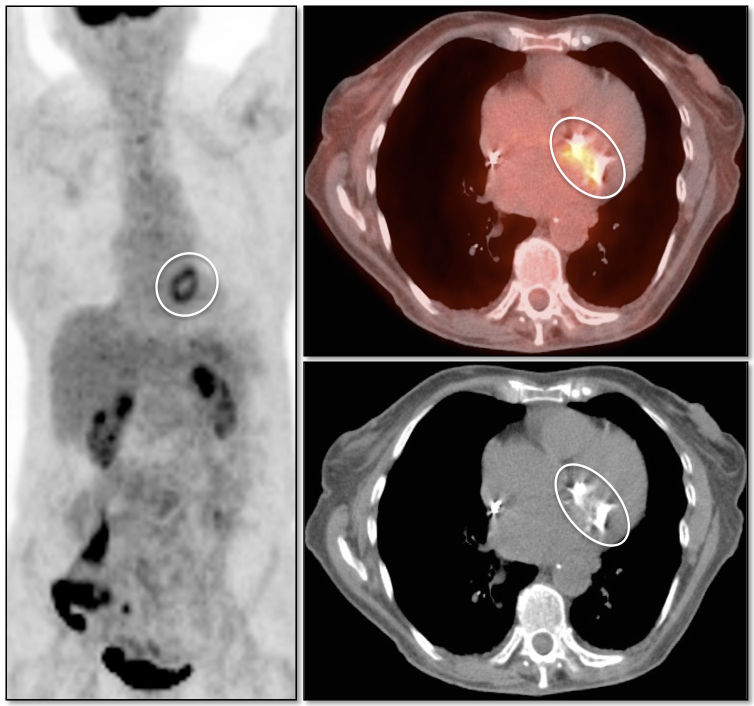

Value of Non-Attenuation Corrected (NAC) Images

Resolving Attenuation Correction Artifacts:

The CT images obtained during an exam are not only used for “anatomic” interpretation. They are also used for “attenuation correction” (AC) of the PET images, generating the much more useful AC PET images used for interpretation.

Unfortunately, attenuation correction of PET images can result in falsely elevated metabolic activity in regions of high CT density (e.g. metallic devices, oral contrast, calcification).

In such cases, these areas must be reviewed on the NAC (non-attenuation correction) images. If these regions are not also hypermetabolic on the NAC images, then their apparent increased FDG-uptake on the AC images is artefactual.

This phenomenon is almost exclusively seen with older PET/CT scanners, as most modern scanners utilize newer algorithms that do not “over-correct” in these areas of increased density.